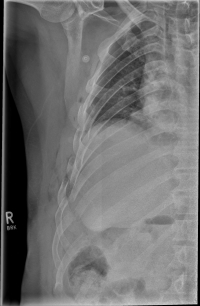

Rib Fractures

The rib fracture is a common injury to the chest. It occurs frequently in (car) accidents, falls during cycling and contact sports. Due to their anatomical position, especially the 4th - 9th ribs are affected.

As a rule, the rib fracture is diagnosed by X-ray. In severe cases or ambiguous X-ray findings, a layer imaging, for example computer tomography (CT), can also be performed.

In some cases, the sharp rib fragments cause lung or outer chest wall injuries. As a result, air can enter the gap between the lung and chest wall and cause a so-called pneumothorax, which must be treated by drainage.

In rare cases, a so-called tension pneumothorax may develop, which under certain circumstances can also be life-threatening. Due to an injury-related valve mechanism, air from the lungs flows into the gap between the lungs and the chest wall, but can not escape. As a result, the organs are shifted in the chest and concentrated, so that the circulatory function is impaired. It requires, in these cases, an immediate delimbing in the hospital or by an emergency physician.